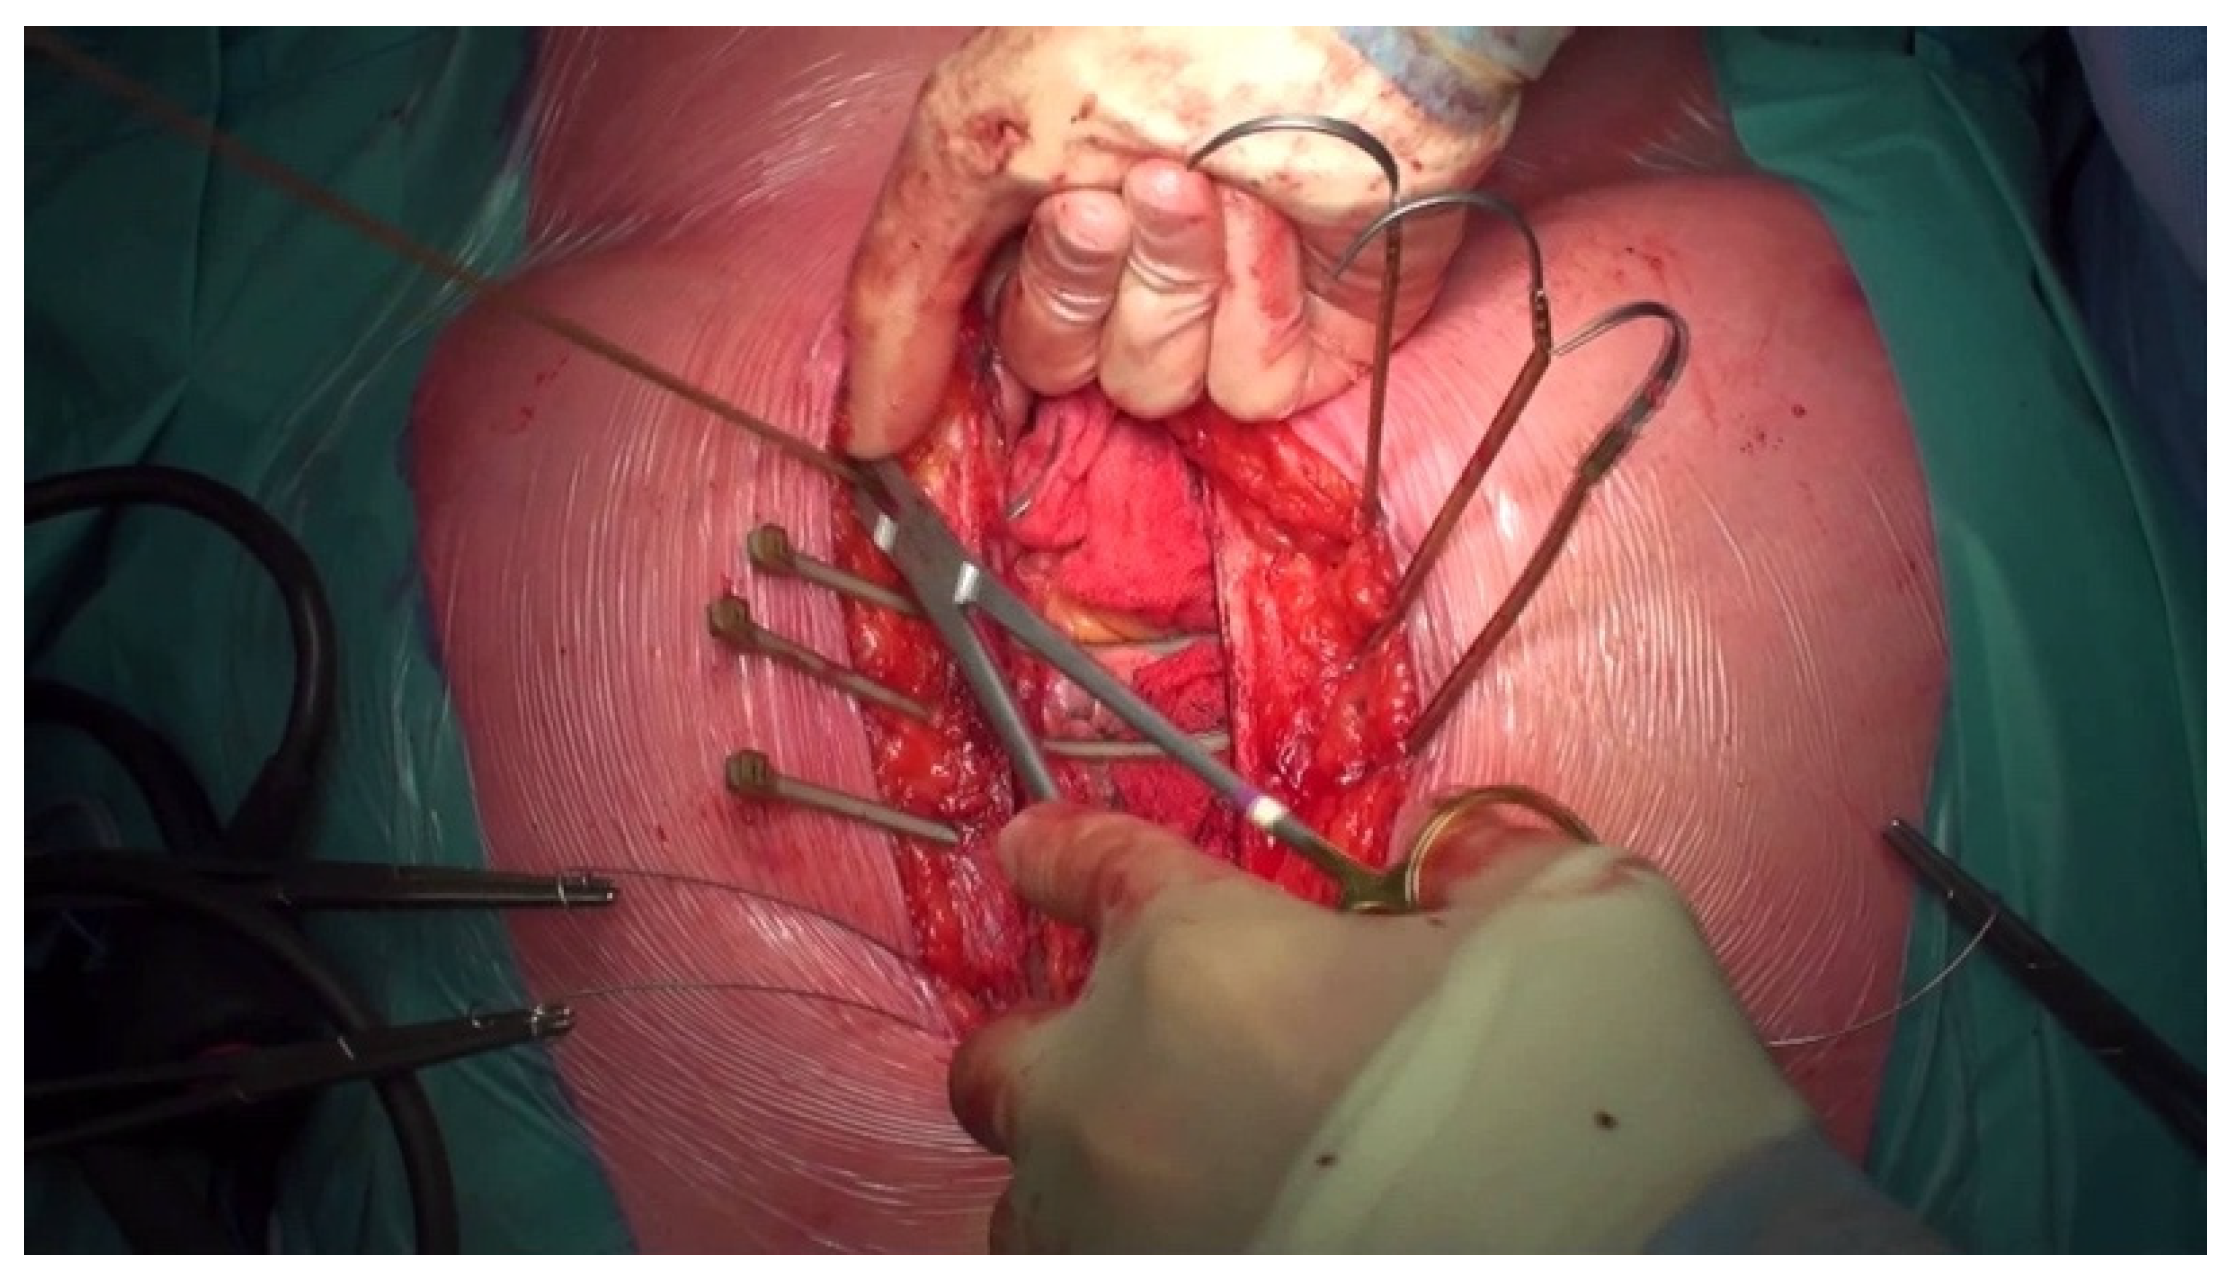

- Jolly, S.; Flom, B.; Dyke, C. Cabled Butterfly Closure: A Novel Technique for Sternal Closure. Ann. Thorac. Surg. 2012, 94, 1359–1361. [Google Scholar] [CrossRef] [PubMed]

- Antonič, M.; Petrovič, R.; Miksić, N.G. Thermoactive Nitinol Clips as Primary and Secondary Sternal Closure after Cardiac Surgery—First Experience in Slovenia. Acta Clin. Croat. 2021, 60, 435–440. [Google Scholar] [CrossRef] [PubMed]

- Stelly, M.M.; Rodning, C.B.; Stelly, T.C. Reduction in deep sternal wound infection with use of a peristernal cable-tie closure system: A retrospective case series. J. Cardiothorac. Surg. 2015, 10, 166. [Google Scholar] [CrossRef] [PubMed][Green Version]